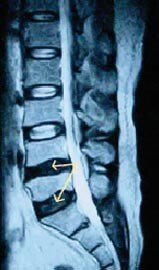

꾀병 오해받는 ‘디스크내장증’

‘가짜 교통사고’ 환자가 종종 사회 문제로 떠오르곤 한다. 반면 환자들 중에는 진짜 환자임에도 불구하고 ‘꾀병’으로 오해받아 고생하는 사람들도 적지 않다. 그중 대표적인 질환이 디스크내장증이다. 디스크내장증은 디스크가 튀어나와 있지…